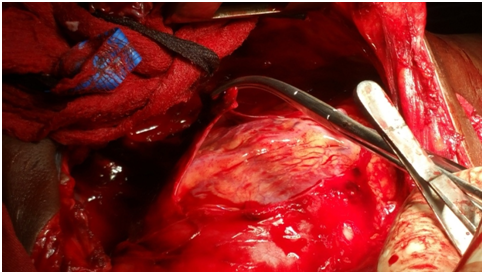

The Thoracotomy and Laparotomy procedures were done. Intraoperative findings were as follows: The patient had a collapsed left lung, There was a penetrating wound in the pericardium in the right heart ventricle. The Sternum was ripped apart and the pericardial tamponade was found and Pericardial opening had to be done. The Penetrated hears was shooting the heart blood out. The stabbed heart was sutured. The abdominal stub wound revealed a tear in the stomach and a linear laceration on the left lobe of the liver. These were repaired.

Figure 4 Pericardium opened.

Figure 5 Identifying stab on heart.